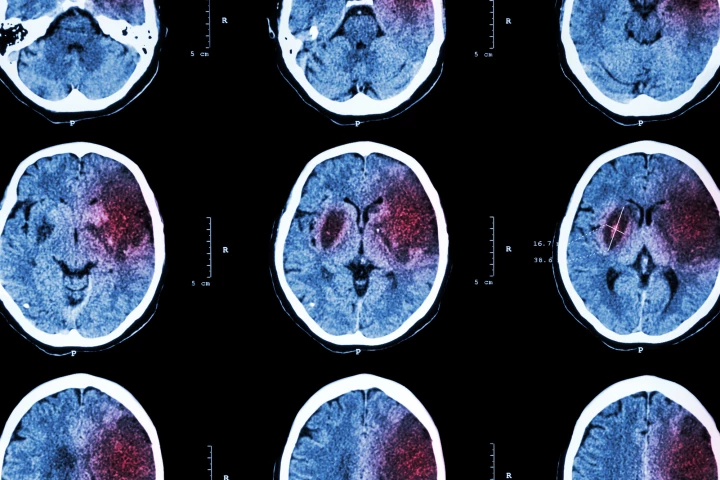

Stroke can be tricky to diagnose as patients don’t always present with classic symptoms, and other conditions can mimic it. Researchers have now developed a machine-learning model that accurately predicts stroke and may make diagnosis easier.